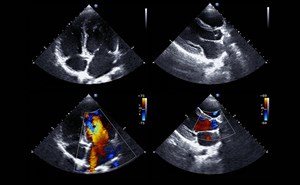

Sound Waves & Sirens: Creating a SonOlympics for EMS Teams Without Prior Ultrasound Training

As a new and enthusiastic member of the ACEP Prehospital, Austere, and Tactical Ultrasound Subcommittee, I’m thrilled to contribute to our mission of expanding the use of ultrasound in prehospital a...